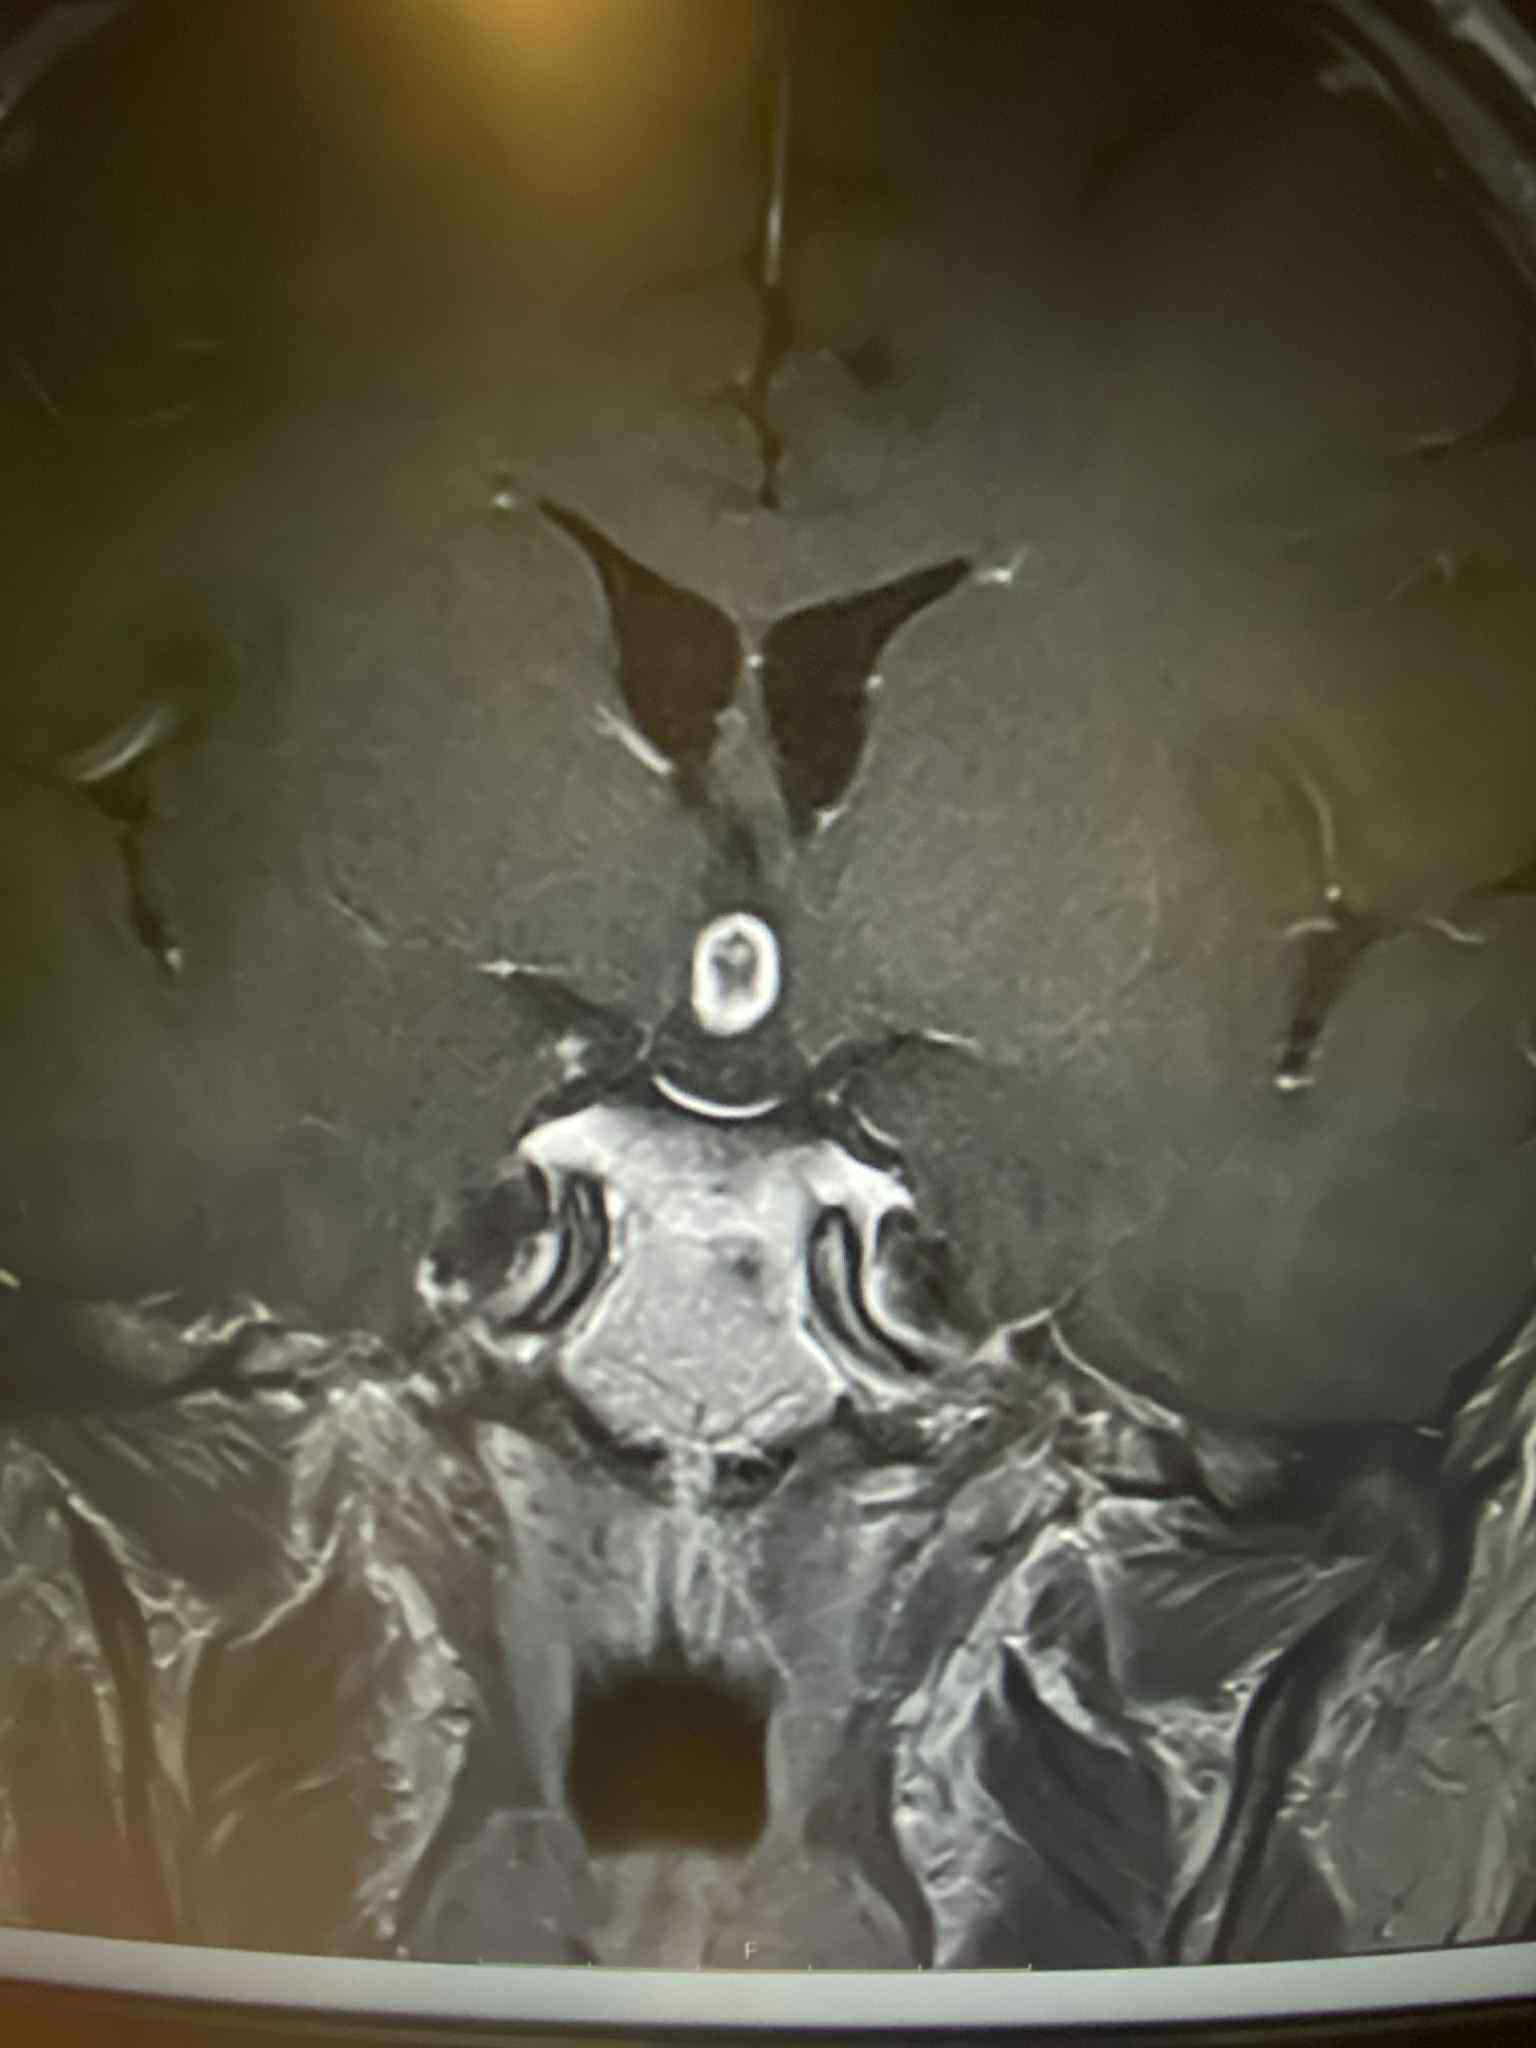

In July he had an MRI done where it showed that he had a tumor on his brain which has grown 4 millimeters as shown by his recent MRI at the start of this month. He has been able to get on an anti-seizure medication but still experiences the nausea, dizziness, headaches and insomnia that the tumor causes. He is at high risk for suffering a stroke due to the tumor pressing up against his hypothalamus.